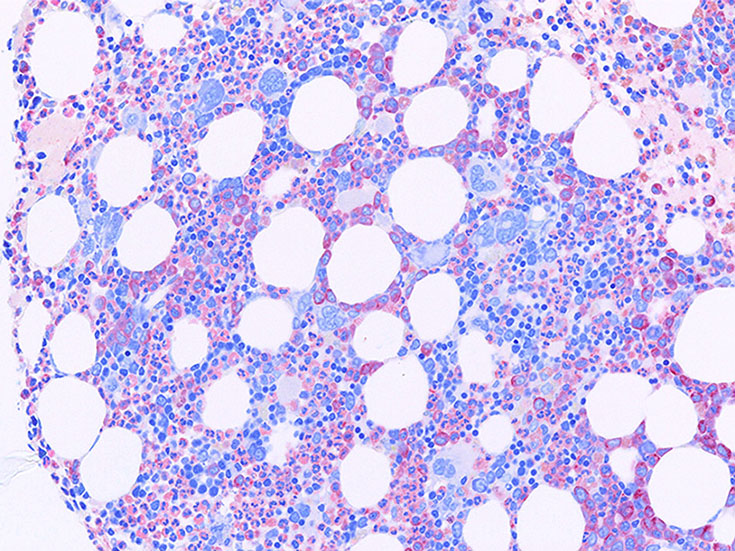

ETを含む慢性骨髄増殖性腫瘍 MPNの多くは, 多かれ少なかれ巨核球増多がみられ, CMLでも巨核球増多が見られる症例が多く, PVはより巨核球の増多が見られる.

CMLの巨核球は小さめで散在性. 凝集はみられない. pureなCMLでは血島が消える.

ET以外のMPNにおける巨核球増加は, 細胞質の広い明瞭な分化をした巨核球であっても, 大型単核や, やや異型的な巨核球の増加が主体である. 血小板凝集はあまり見られない.*12